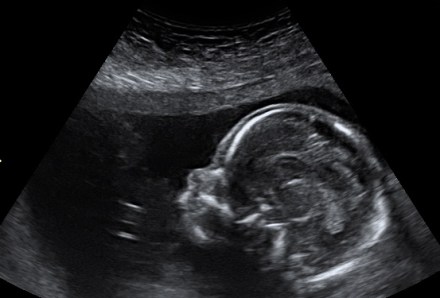

I had my 20 week scan yesterday and these images gave me a sneaky peek into yet, another soul. xx